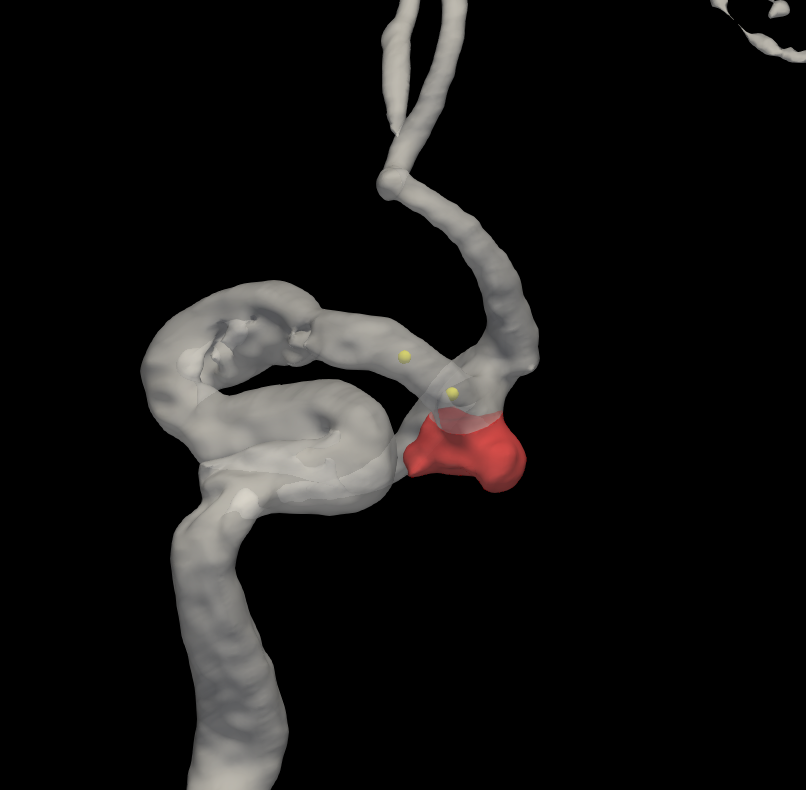

图2 脑血管三维重建及动脉瘤自动分割

图3 3D形态学参数自动测量